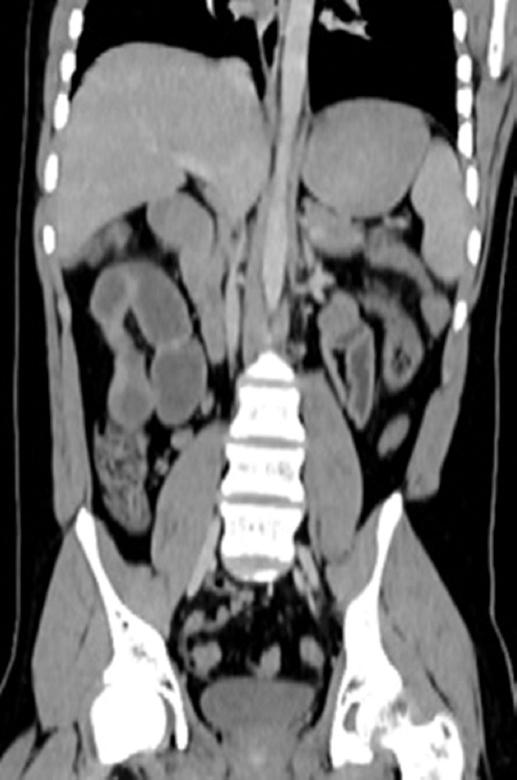

The CT reports noted intestinal obstruction and ileus secondary to foreign body ingestion (Fig. 2).